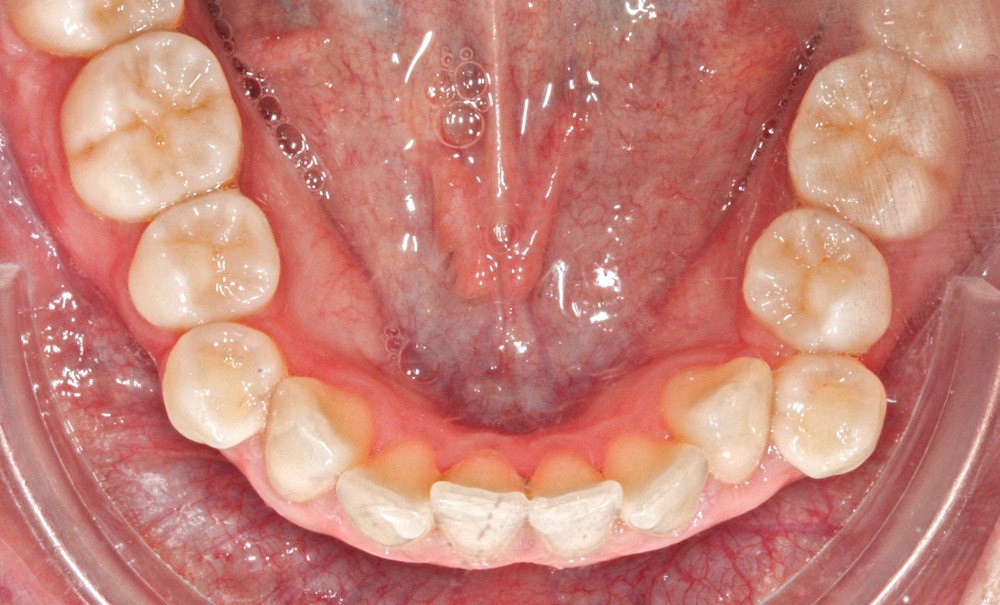

L’examen intra-arcade met en évidence une hygiène bucco-dentaire irréprochable, favorable à un traitement en technique linguale. Le phénotype parodontal est fin dans la région incisivo-canine mandibulaire. L’encombrement est estimé à 8 mm à la mandibule et à 4 mm au maxillaire (fig. 2). Les arcades ont des formes similaires, en U. Les rapports inter-arcades mettent en évidence une classe I d’Angle…